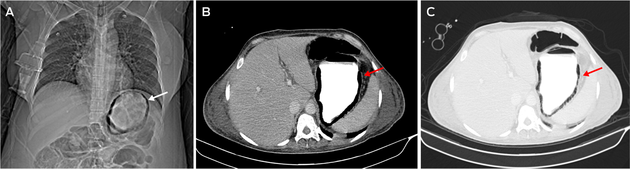

Gastric pneumatosis, a rare condition characterised by the presence of air in the gastric wall, may be caused by infection or ischaemia.1 A 47‐year‐old woman who had undergone a Hartmann procedure for sigmoid colon perforation, developed sepsis a week after surgery. Blood cultures grew Corynebacterium diphtheriae and Pseudomonas aeruginosa. A computed tomography scout image of the abdomen showed circumferential gas within the gastric wall (Figure, A). Axial images in soft tissue (Figure, B) and lung windows (Figure, C) delineated the extent of gastric pneumatosis. There was no evidence of portal venous gas. Gastric pneumatosis can be subdivided into gastric emphysema (typically self‐limiting) or the more aggressive emphysematous gastritis.2